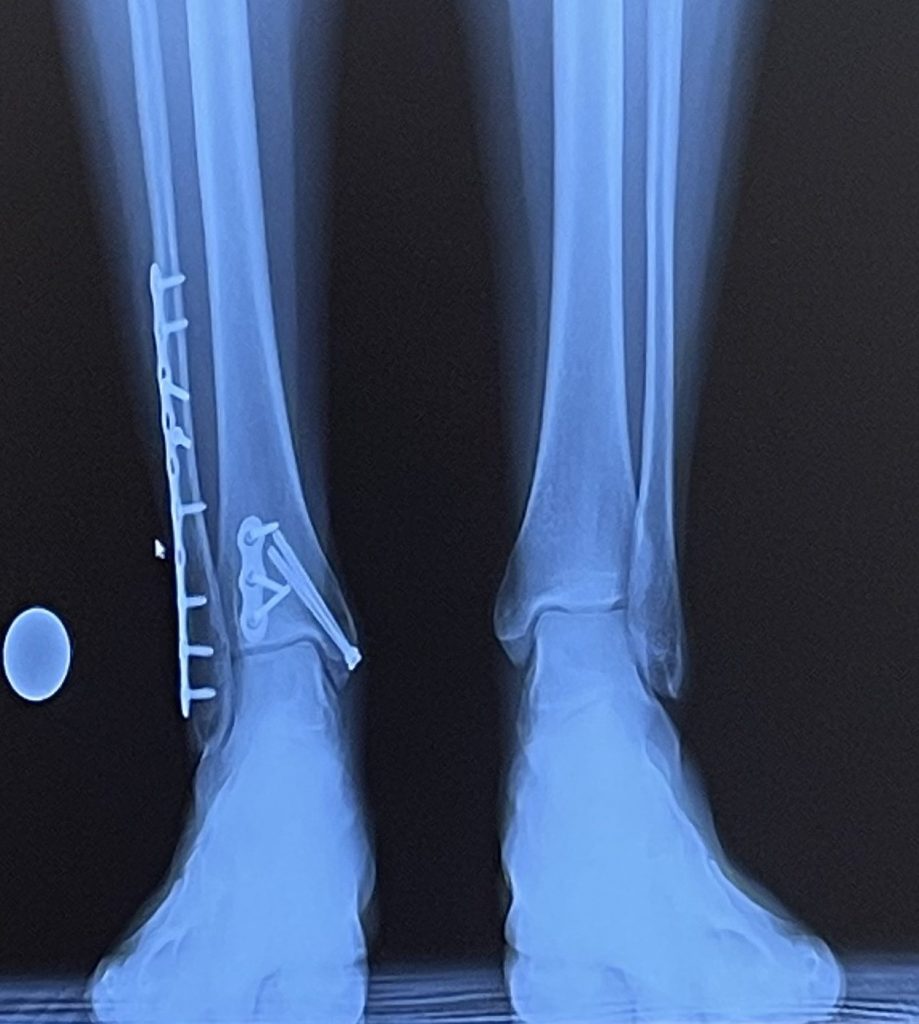

I’m a 31 year old working mom of 2 and I was about 10 months postpartum with my first baby when I fell down the stairs in my house carrying a basket of my son’s laundry. The minute I landed on my right ankle I knew it was broken but had no idea it was essentially shattered and was terrified to learn in an emergency room I would need surgery to repair it.

Now a year later, I’m in a place I could never have imagined the first day I hobbled into the office on crutches. I have no pain or swelling in my ankle and the only evidence of the magic Dr. Cody worked can be seen on my x-rays. I love to show them off to my friends and colleagues occasionally for shock value.